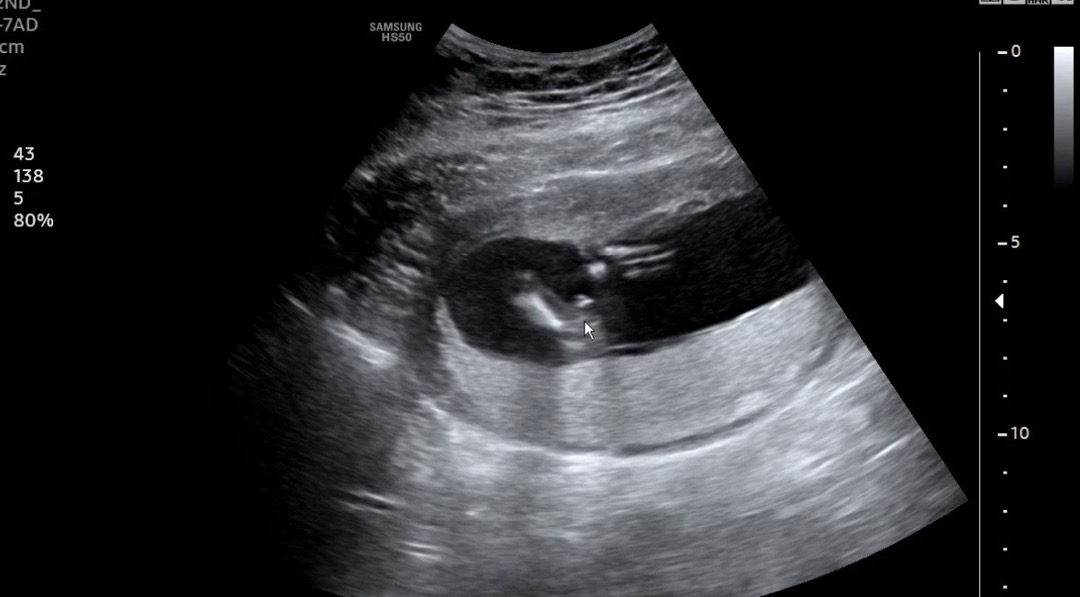

14주0일 성별봐주세요!

병원 간김에 선생님이 다리 사이 봐주셨는데 아들로 생각하고 있으라고 하신…ㅎㅎ 다리 사이 하얀 저 부분이 🌶️일까요? 14주에 딸이면 다리사이가 완전 매끈한지 궁금해용 🥹

쪼꼼 애매하네용 ㅠㅠ 탯줄일 수도 있어서 다른사진은 없나용?.?